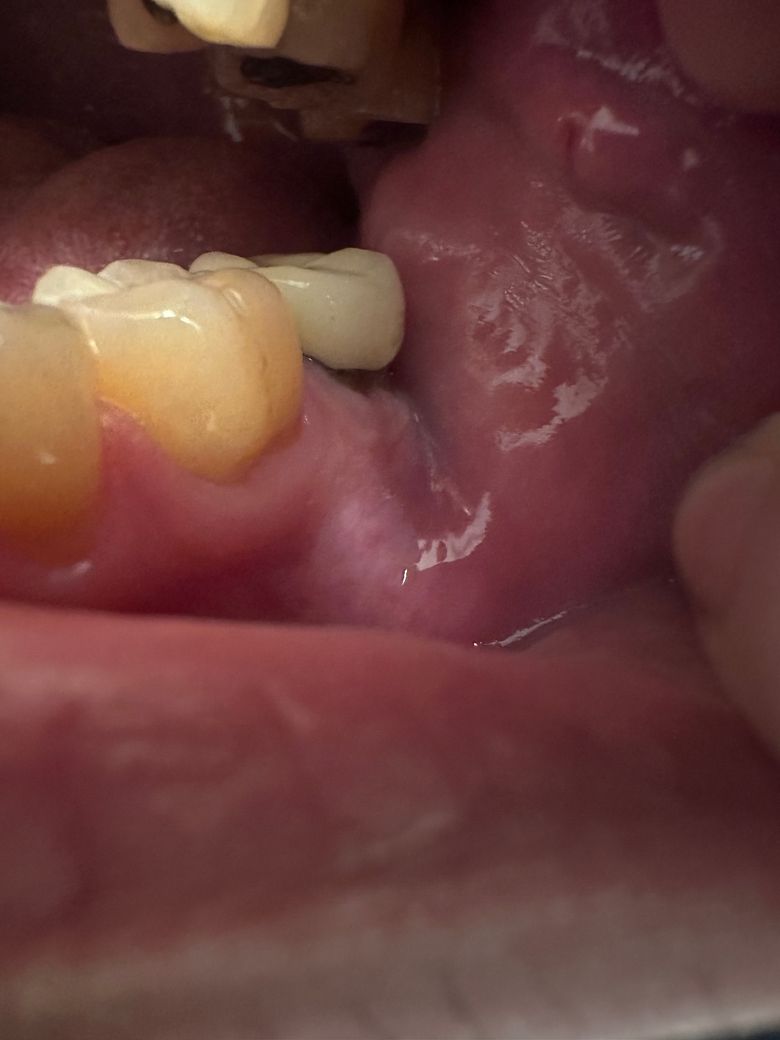

안녕하세요. 포세린 크라운을 2009년에 했는데요. 가장 안쪽 어금니에 pfm으로 했습니다. 입안을 살펴보던 중 메탈 부분이 많이 보이는걸 최근에 확인했는데 크라운을 오래 방치한게 아닐까 싶어서요. 잇몸도 좀 내려간거 같은데 혹시 문제가 될만큼 많이 내려간걸까요? 스케일링을 약 한두달전에 받을땐 별다른 소견은 없었습니다. 큰 통증도 없기는 합니다.

• 1번 째 사진

잇몸이 내려가면서 치아가 많이 노출된상태 같습니다. 엑스레이를 찍어보시고 나서 문제가 없다면 크라운을 다시 하시는게 좋을것같습니다.

잇몸퇴축이 심하네요 크라운 자체 기능적으론 큰 문제없습니다 신경치료된 치아라면 저렇게 뿌리 드러났다고 시리지도 않고요 다만 잇몸관리는 정기적으로 받으셔야 합니다